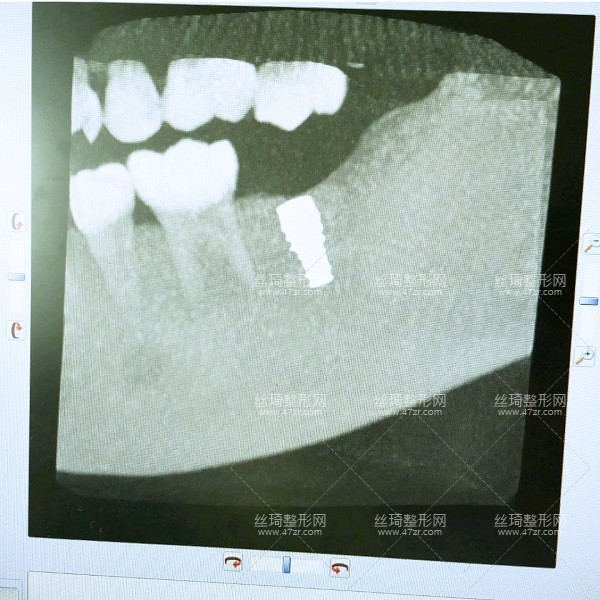

2.種植牙案例

手術(shù)第1天

一直不知道什么原因?qū)е挛业难罆?huì)這樣,多方咨詢之后選擇了長(zhǎng)沙中諾口腔進(jìn)行整牙,過去檢查了一下,醫(yī)生說我可以搞種植牙,但是以前補(bǔ)過的牙現(xiàn)在顏色變了,需要重新做,看來是個(gè)大工程啊,啊啊啊啊~~~

手術(shù)第2天

今天過來醫(yī)生檢查了我的牙床和骨組織,情況不錯(cuò),可以直接調(diào)節(jié)。首先助理幫我清潔口腔,護(hù)士準(zhǔn)備手術(shù)室,清理過口腔后,吃了止痛藥,然后進(jìn)手術(shù)室,然后躺到牙椅上,就打麻藥的時(shí)候有點(diǎn)緊張,種牙很輕松,全程一個(gè)半小時(shí)。出來后,冰敷了,告訴我注意事項(xiàng),讓我一周后來拆線。